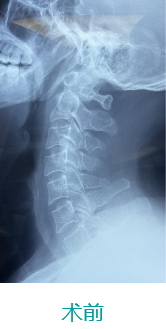

天玑II脊柱手术—颈椎手术

天玑II 辅助颈椎椎弓根螺钉内牢靠术

基本情形:患者男,,,,,49岁,,,,,枢椎骨折

病例泉源:北京积水潭医院